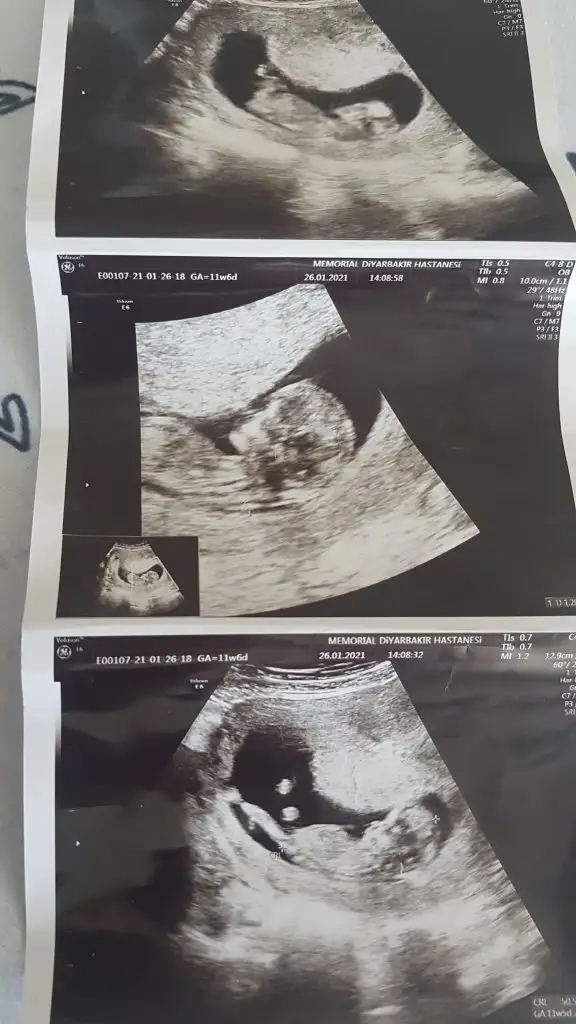

dün 2 li tarama testine girdim bebeğim uyuyordu doktor cinsiyet tahmini yapmadı renkli ultrasonografi görüntülerim var, bu resimlere göre cinsiyet tahmini yapabilirmsiiniz , bu ikinci gebeliğim 8,5 yaşında bir kızım var

mesajım görünmüyor mu acaba cevap alamadım, 12+5 de 2 li tarama yaptırdım, cinsiyet tahmini yapmadılar, bu görüntüler üzerinden tahmin yapabilirmisiniz